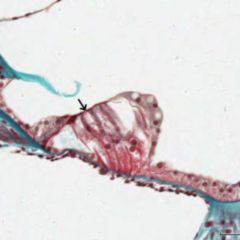

Nell'avambraccio, la membrana collega il radio e l'ulna. È l'elemento principale della sindesmosi fra radio e ulna, un'articolazione fibrosa fra i due ossi.

La membrana divide l'avambraccio in due sezioni, anteriore e posteriore, serve come punto di inserimento per i muscoli e scarica le forze dal radio sull'ulna e sull'omero.

Nella gamba, la membrana collega la cresta interossea della tibia e quella del perone. La membrana presenta fori per il passaggio di vasi e nervi e separa i muscoli della loggia anteriore della gamba da quelli della loggia posteriore.